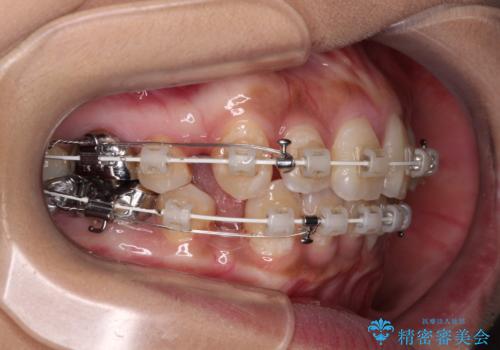

- 矯正装置

- 審美装置

上下ともに歯列が前方に突出していたため、上下左右の第一小臼歯4本を抜去し、ワイヤー装置による矯正治療を行うこととしました。

4本の歯を抜歯したことで、飛び出していた口元が引っ込み、横顔が大きく改善されました。